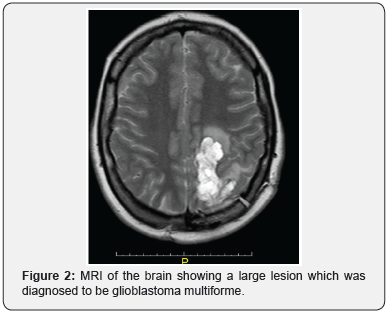

Over the next three years she had multiple new malignancies: Urothelial atypia detected on routine screening cystoscopy, glioblastoma multiforme (Figure 2) detected by brain MRI, endometrial adenocarcinoma after developing menorrhagia, high grade ovarian adenocarcinoma after an episode of lower abdominal pain, and recurrent adenocarcinoma of the colon found on screening colonoscopy. KP has undergone medical and surgical management including intravesical mitomycin, craniotomy with tumor resection, radiation and chemotherapy, and multiple colectomies with revisions (Figure 3).